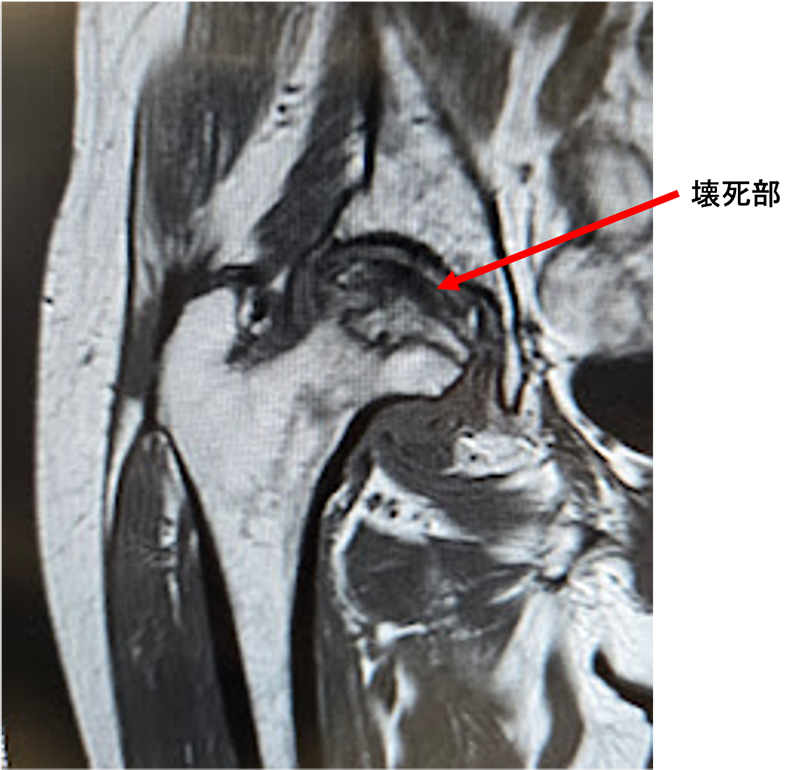

〈右股関節のMRI〉

骨頭壊死により、大腿骨の骨が潰れ、非常に疼痛が強く、歩行困難であったために早期の手術を予定。当院にて人工股関節全置換術(THA)を施行。アプローチはAMIS(前方最小侵襲手術)で行い、術中に神経ブロックを行い術後の痛みをコントロールし、術翌日から歩行訓練をはじめ、10日程度で退院となりました。

股関節の中心である大腿骨頭が壊死してつぶれるために痛みを生じる病気です。アルコールの多飲やステロイドの使用に関連しているとも言われていますが、いまだにはっきりしておらず国の難病に指定されています。進行すると大腿骨頭が陥没を起こし、歩行が困難になります。症状が強ければ人工股関節置換術が必要になることがあります。